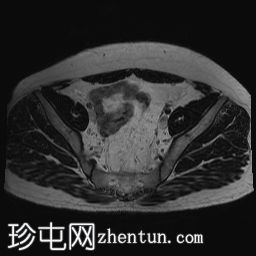

冠状位PD序列

脂肪抑制序列

双侧睾丸均未在阴囊内显露,而是位于盆腔腹股沟管上部。

-左侧睾丸大小为2.6 cm x 1.6 cm x 2 cm。

-右侧睾丸大小为2.6 cm x 1.2 cm x 1.1 cm。

双侧隐睾(睾丸未降)位于盆腔腹股沟管上部。